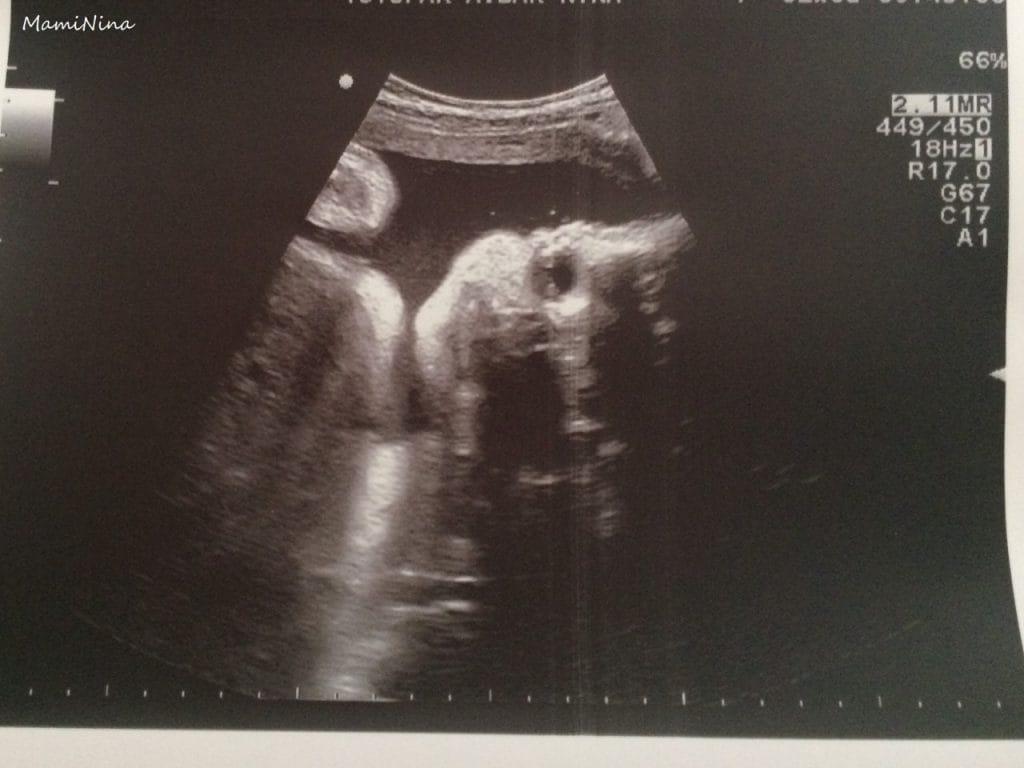

Nato mi je izmerila do kam je zrastla maternica in punčko pregledala z ultrazvokom. Vprašala me je kako se kaj odločam glede poroda, glede na prvi porod seveda. Moje mnenje ostaja, da v primeru medenične vstave napravimo carski rez, če pa bo vodilni plodov del glava, potem pa vsekakor po klasični poti. Med ultrazvokom mi je povedala, da je že obrnjena z glavo navzdol, v super poziciji. Ko je opravila vse meritve mi je pokazala njen mali obrazek (naredila mi je tudi slikico in jo vstavila v materinsko, da sta lahko mali obrazek videla tudi moja najdražja in pokažem ga seveda tudi vam), trebušček, srček in nogice. Torej vse je super. Mere so nekaj malega manjše od povprečja, ampak tudi pri prvi je bilo tako, ki se je potem vseeno rodila s povsem povprečnimi merami. Trenutno naj bi imela 1840 g.